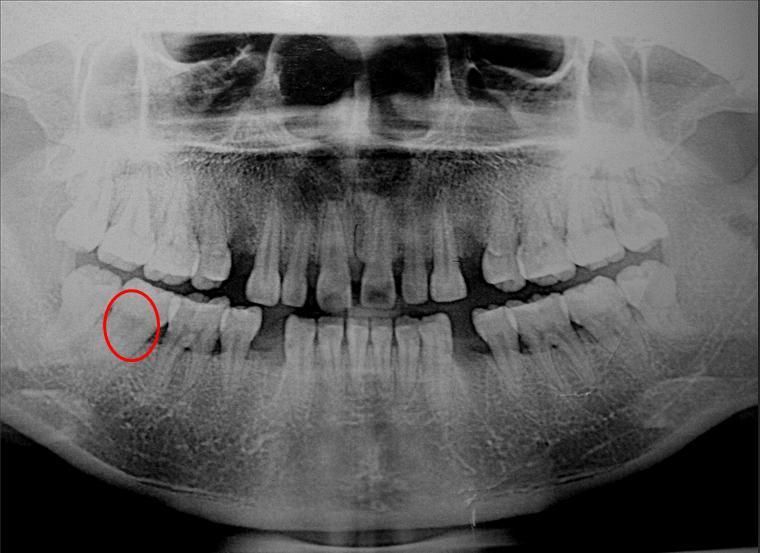

口腔科的专家看过来,看看能不能正畸(附上x片)